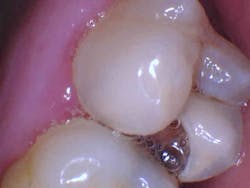

In the case below, tooth No. 2 was diagnosed with symptomatic irreversible pulpitis and symptomatic apical periodontitis with a mesial marginal ridge fracture due to extensive caries (figure 1). Root canal therapy and a full coverage crown were recommended and the patient accepted.

The carious tissue was removed, followed by the endodontic procedure and subsequent placement of the build-up. Despite the deep extent of mesial decay, a clear and accurate scan was achieved (figure 2).

The iTero scanner was able to clearly define the delineation between the soft and hard tissue as can be seen in this image of the digital die trim (figure 3). Radiographs were captured on delivery revealing a clinically acceptable outcome for the patient (figure 4). Direct restorations were completed on teeth Nos. 3 and 4 during this visit.